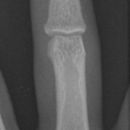

Mittelgliedbasisfraktur